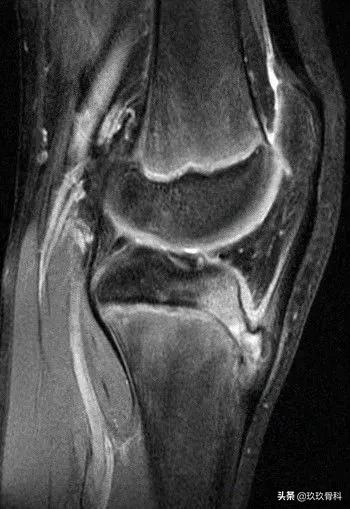

三、MRI

分为五期:正常、早期、进展期、终末期、愈合期。

1.正常: 尽管患者已有症状,但是MRI显示正常;

2.早期: 无炎症表现,无二次骨化中心撕脱;

3.进展期: 二次骨化中心部分软骨撕脱;

4.终末期: 可见游离骨片;

5.愈合期: 胫骨结节骨性愈合,无游离骨片。

国外一些研究者认为MRI检查是诊断胫骨结节骨软骨炎最好的方法,特别是能发现早期和进展期病灶,MRI检查可以反映胫骨结节骨软骨炎疾病过程,而其他检查方法无能为力。但是MRI检查比较昂贵且不普及这样就限制了它在国内诊断胫骨结节骨软骨炎的应用。